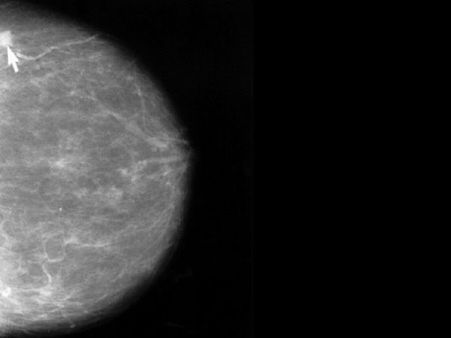

Treatment Options For Fibrocystic Breast Disease

There are several treatment options for fibrocystic breasts. Read to know the best treatment for fibrocystic breast disease.